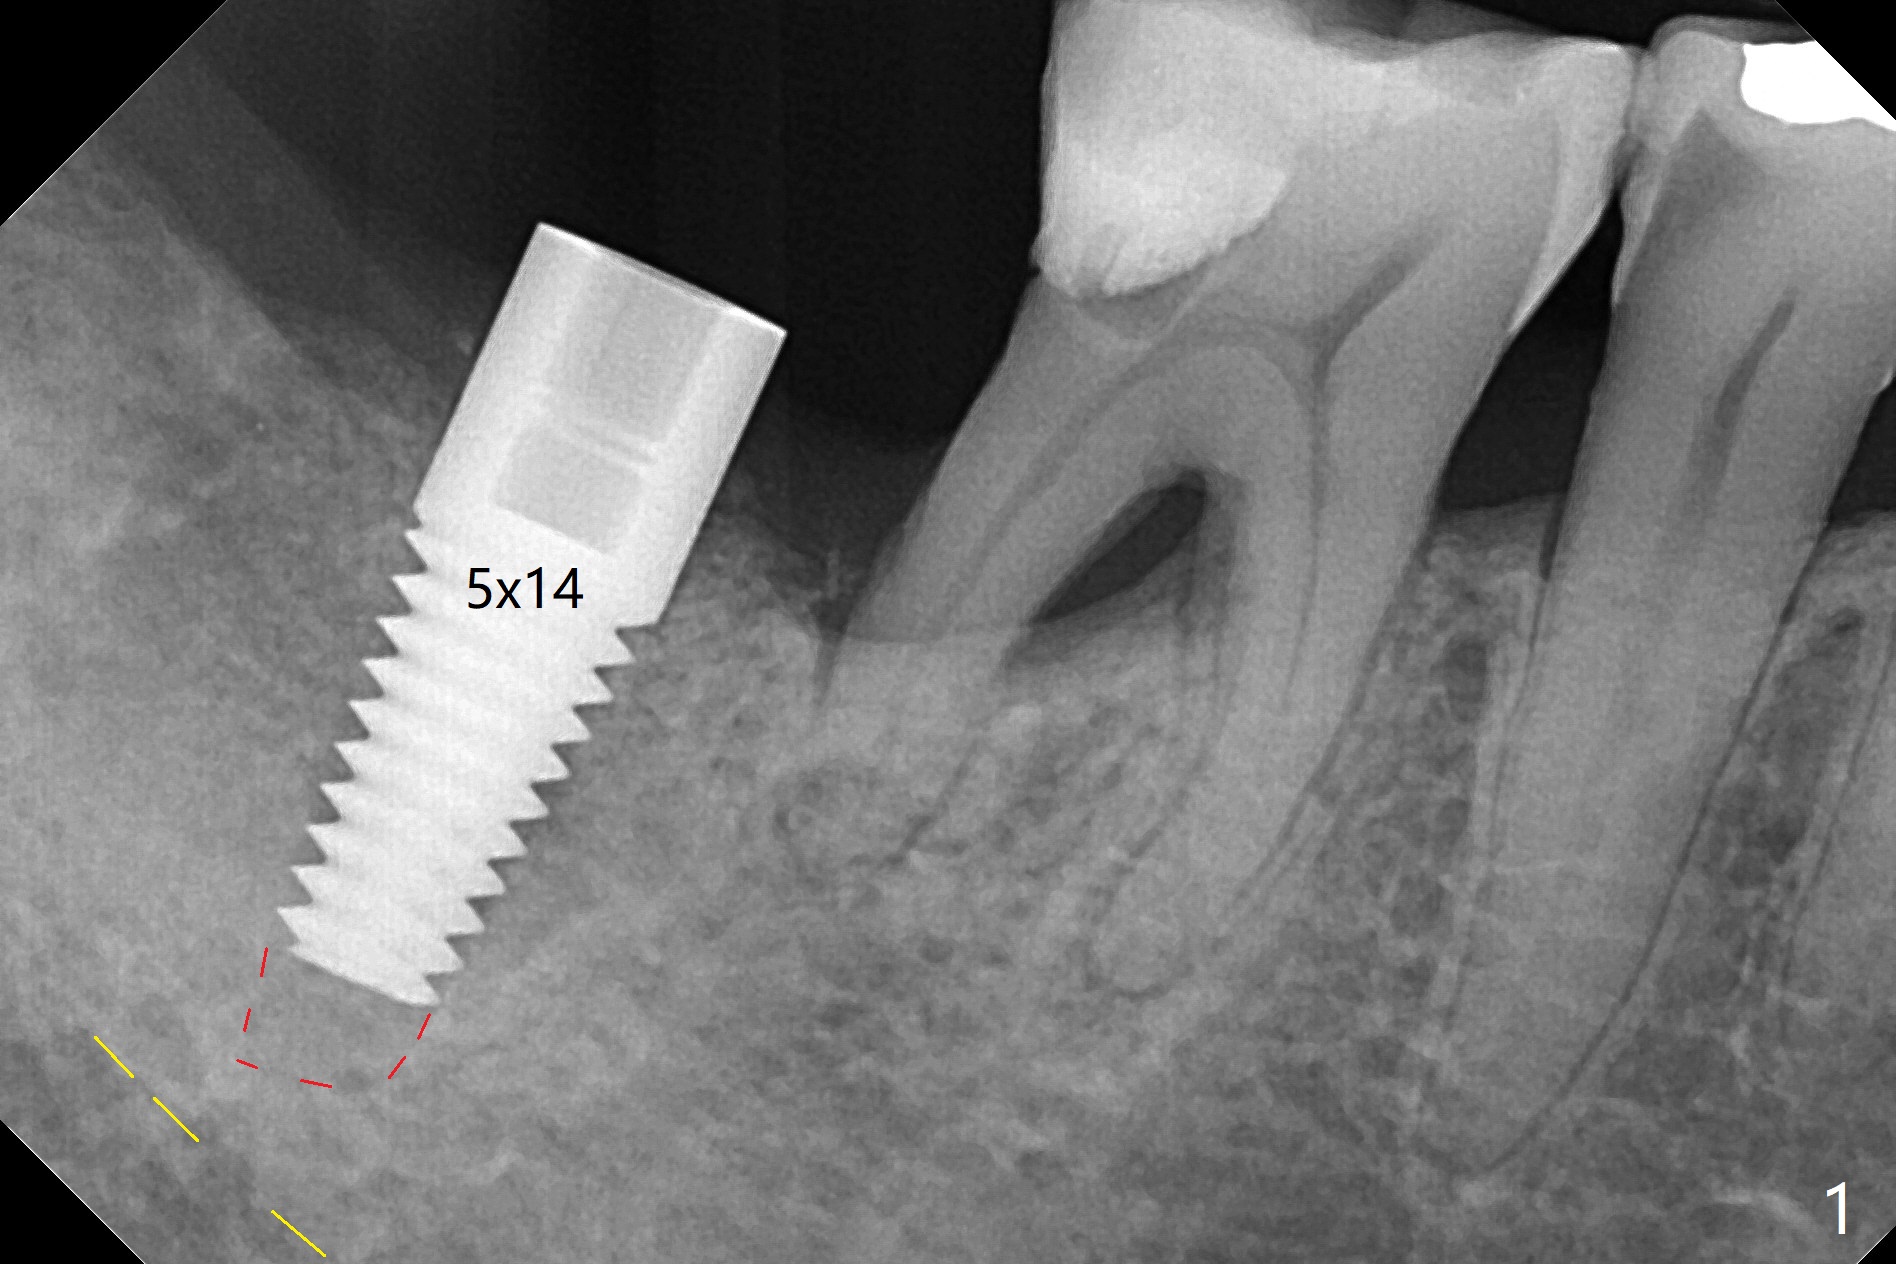

59岁女,吃素,右下7拔除植骨(使用血小板因子),术后7个月证实颊侧骨板再生,但是骨质密度低,导板取模后,家庭医生诊断骨质疏松症,开始服用钙片和Fossamax,后者每周一次,已经四周了。今天她回来植牙(术后10个月),术前决定使用小号钻头,术中的确发现骨质疏松,几乎没有骨削。4毫米钻头完成钻洞,4.5毫米报废植体没有什么稳定性,5毫米植体植入(部分徒手)扭力~45 Ncm(图一(红虚线:根尖钻洞;黄虚线:下齿槽管)),最后将植体种深些(图二:箭头)。